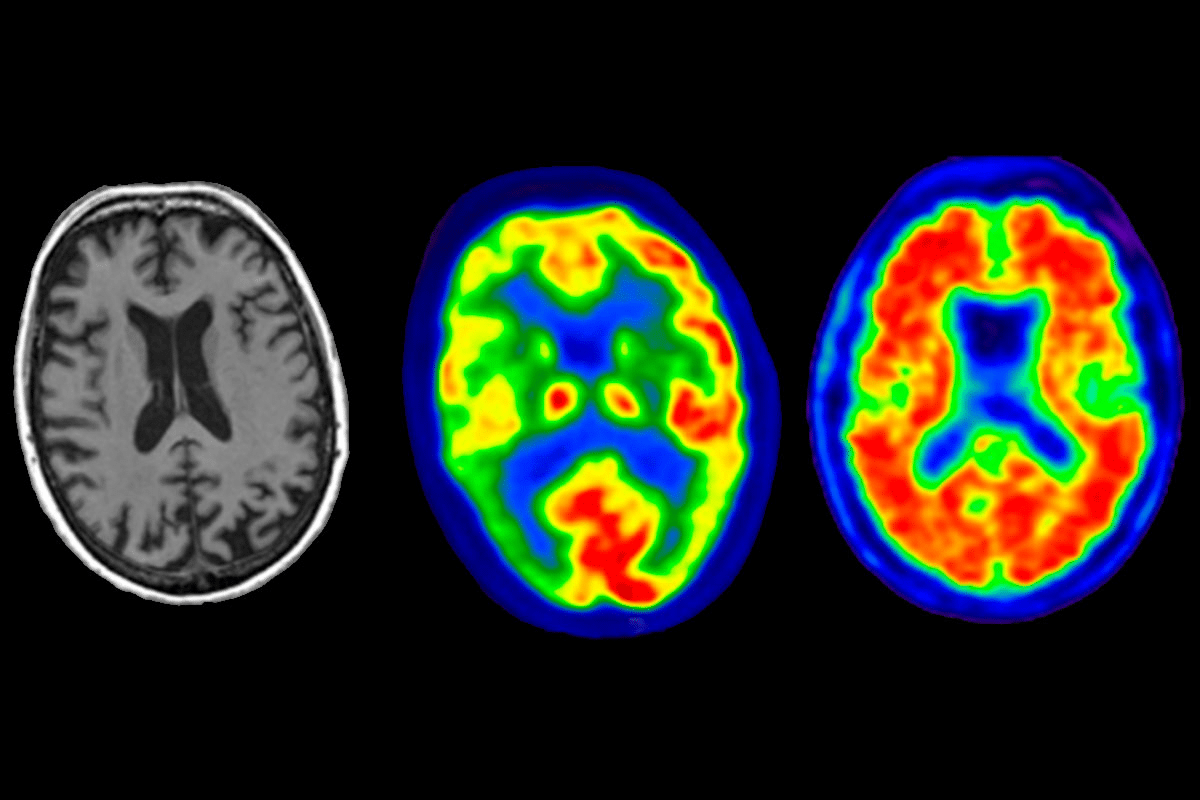

- Lip smacking can be associated with dementia and other neurological conditions.

As more people age, it’s key to understand why some elderly people smack their lips. This behavior is seen in those with dementia or on certain meds. It’s a sign of involuntary mouth movements.

Dementia-Related Movement Disorders

Dementia is a decline in cognitive function, including memory loss and confusion. Certain types of dementia, like frontotemporal dementia, can cause involuntary movements, including lip smacking and other oral dyskinesias.